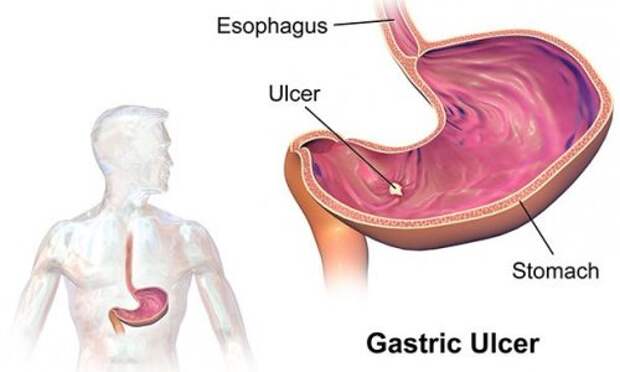

14. Возникновение пептических язв не связано со стрессом или неправильным питанием. Исследователи выяснили, что возбудителем этого недуга является бактерия под названием хеликобактер пилори (Helicobacter pylori).

14. Возникновение пептических язв не связано со стрессом или неправильным питанием. Исследователи выяснили, что возбудителем этого недуга является бактерия под названием хеликобактер пилори (Helicobacter pylori).